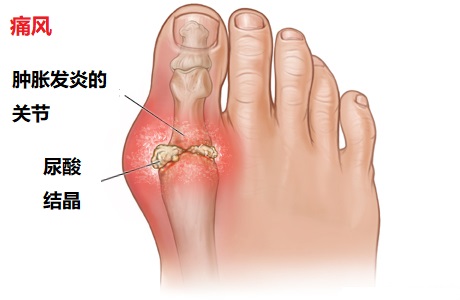

痛风也会引起急性滑膜炎。一般患者有高尿酸血症。尿酸结晶石骤然增加,刺激滑膜诱发急性炎症。常于夜里发作,出现剧烈的关节疼痛和肿胀。关节迅速红、肿、热、痛。最常见第一跖趾关节(大脚趾)、足跗骨关节、踝关节和膝关节。发作原因常为饮食过饱、外伤、手术、饮酒过量、降尿酸治疗等。对症用药1-2天就明显减轻,3-10天自行消退缓解。多次急性单关节发作后,部分患者出现慢性非对称性滑膜炎。